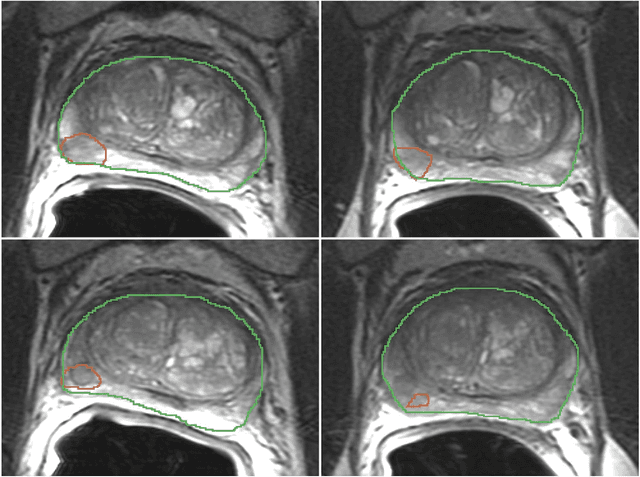

Abstract:In this study we assessed the repeatability of the values of radiomics features for small prostate tumors using test-retest? Multiparametric Magnetic Resonance Imaging (mpMRI) images. The premise of radiomics is that quantitative image features can serve as biomarkers characterizing disease. For such biomarkers to be useful, repeatability is a basic requirement, meaning its value must remain stable between two scans, if the conditions remain stable. We investigated repeatability of radiomics features under various preprocessing and extraction configurations including various image normalization schemes, different image pre-filtering, 2D vs 3D texture computation, and different bin widths for image discretization. Image registration as means to re-identify regions of interest across time points was evaluated against human-expert segmented regions in both time points. Even though we found many radiomics features and preprocessing combinations with a high repeatability (Intraclass Correlation Coefficient (ICC) > 0.85), our results indicate that overall the repeatability is highly sensitive to the processing parameters (under certain configurations, it can be below 0.0). Image normalization, using a variety of approaches considered, did not result in consistent improvements in repeatability. There was also no consistent improvement of repeatability through the use of pre-filtering options, or by using image registration between timepoints to improve consistency of the region of interest localization. Based on these results we urge caution when interpreting radiomics features and advise paying close attention to the processing configuration details of reported results. Furthermore, we advocate reporting all processing details in radiomics studies and strongly recommend making the implementation available.